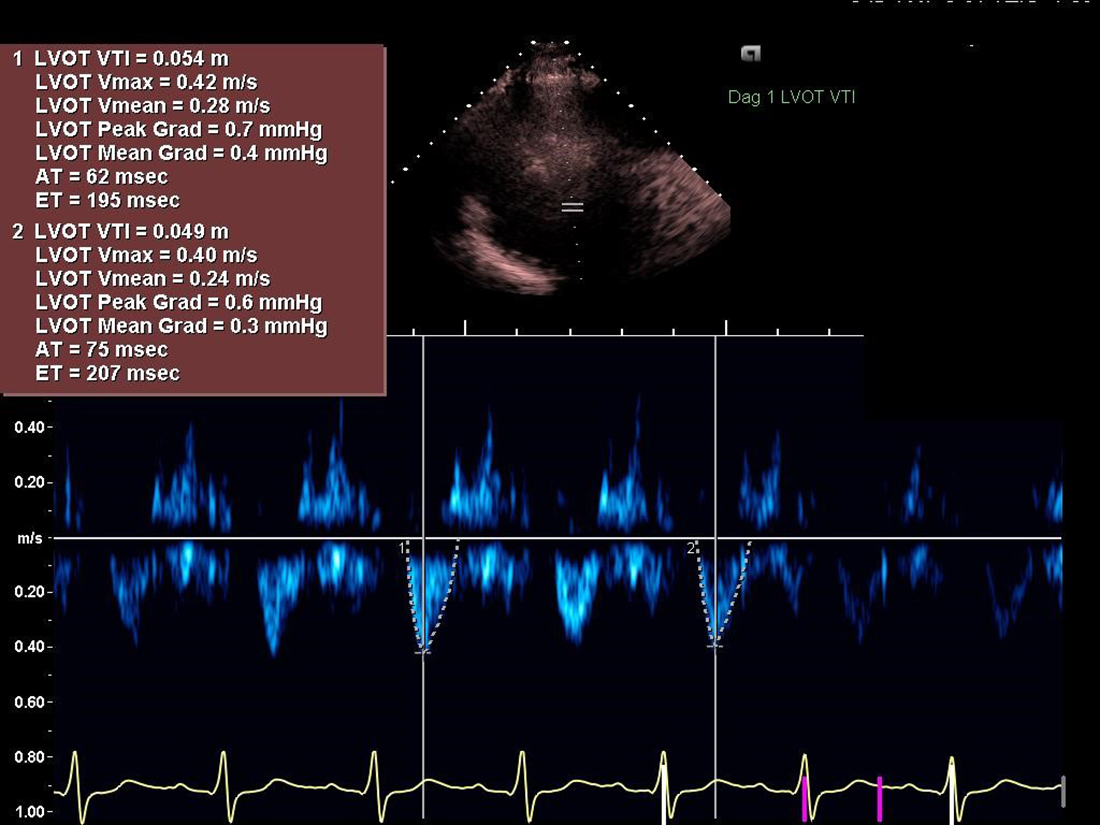

Hon bekräftade intag av tre gram venlafaxin depåtabletter som vid allvarlig SNRI-intoxikation. Under IVA-övervakning fick hon två nya kramper som bröts med lorazepam. En ihållande takykardi noterades; metoprolol- och magnesiuminfusion startades. Hon blev gradvis hypoton, och strax innan noradrenalin gavs fick hon ett ventrikelflimmer som bröts efter 10 minuters HLR med defibrillering och adrenalin. NT-proBNP 2 330 ng/l och troponin nr 2: 28 ng/l. Akut ekokardiografi (Figur 1, 2) kunde visuellt och kliniskt stämma med svår takotsubo. Hon var hemodynamiskt instabil trots noradrenalin och dobutamin och flyttades till Linköping för Ecmo-beredskap. Där lades introducer för Ecmo och hemodynamiken följdes noga med upprepade ekokardiografier. Höga koncentrationer av den aktiva metaboliten O-desmetylvenlafaxin rapporterades: 108 580 nmol/l (referensintervall 350–1 500). Levertransaminaser hade nu stigit påtagligt: ASAT 48 µkat/l, ALAT 45 µkat/l. Inotropi med milrinon tillades på grund av fortsatt cirkulationssvikt. Ställningstagande till start av Ecmo gjordes kontinuerligt, och hemodynamiken förbättrades successivt; ekokardiografi på morgonen visade dramatisk förbättring med närmast normal högerkammarfunktion och vänsterkammarfunktion som gått från uttalat till måttligt nedsatt. Patienten bedömdes inte längre behöva Ecmo-beredskap. Vasopressorer sattes ut och milrinon byttes till en dygnsdos levosimendan. Följande tio dagar gjordes tre ekokardiografier med en slutligen normal vänsterkammarfunktion och obetydlig mitralisinsufficiens. Leverprov och NT-proBNP normaliserades. Efter 14 dagar åkte hon hem. Vid samtal efter en månad mådde hon bättre och var tillbaka på både gymmet och arbetet.

Figur 2. Ekokardiografi visade en uttalat nedsatt systolisk vänsterkammarfunktion; EF biplan cirka 15–20 procent. Utbredd väggrörelsestörning med akinesi i samtliga mid- och apikala segment, hypokinesi längst basalt. Måttlig mitralisinsufficiens. LVOT-VTI (slaglängden av vänsterkammarens utflödestrakt): 6 cm, som vid mycket låga slagvolymer. Uttalat nedsatt högerkammarfunktion. TAPSE (tricuspid annular plane systolic excursion) uttalat sänkt, 5 mm. Fysiologiska kliniken i Norrköping har bidragit med ekokardiografibilden.